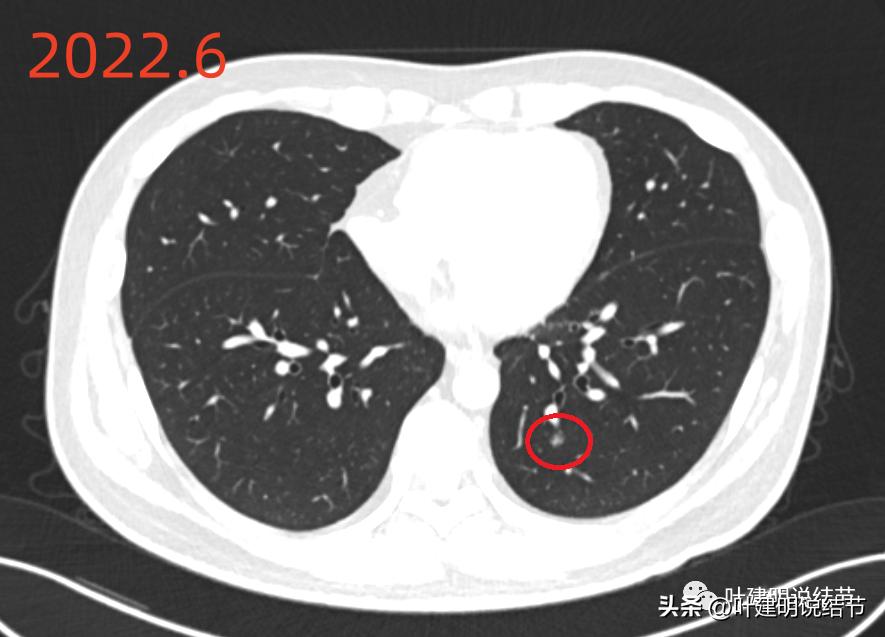

2022年6月的影像:

左下叶主病灶(以下称病灶B)位于后基底段,是磨玻璃密度的,有微小血管进入,轮廓较清,像肿瘤范畴的结节些,原位癌可能性较大点,但目前较小。

先看2022年6月的片子时,感觉左下叶红色圈起来的像原位癌,桔色圈起来的像不典型增生可能性大些。但回顾2019年的片子,当时有肺炎,如绿色圈起来的范围内都是炎症性的,那时候这两个病灶也有,但红色这处当时瘤肺边界模糊点,桔色这处密度比现在感觉要高点,又结合当时炎症过,所以总体看来,桔色的考虑慢性炎性结节可能性大;红色的虽不能除外原位癌,但也无法除外炎性,至少风险应该不算高,如果再随访下也可以的。若手术,红色的要后基底段切除,桔色的要前内基底段切除,就留下外基底段与背段感觉有些孤立;若均楔形切除也是可以的,但若均是炎性,则不划算,我个人意思仍是风险不大情况下,再观察下,反正危险不大嘛!